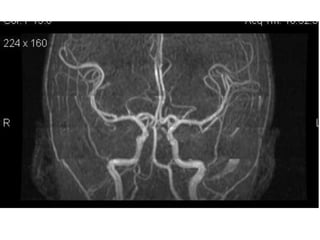

NORMAL MRA

Arteries of the brain (lateral view) - MRA

Arteries of thebrain (cranial view) - MRA 1. Anterior cerebral artery 2. Anterior communicating artery 3. Basilar artery 4. branches (in insula) of middle cerebral artery 5. Cavernous portion of internal carotid artery 6. Cervical portion of internal carotid artery 7. Genu of middle cerebral artery 8. Intracranial (supraclinoid) internal carotid artery 9. Middle cerebral artery 10. Ophthalmic artery 11. Petrous portion of internal carotid artery 12. Posterior cerebral artery 13. Posterior cerebral artery in ambient cistern 14. posterior cerebral artery in interpeduncular cistern 15. Posterior communicating artery 16. Posterior inf cerebellar artery. 17. Quadrigeminal portion of posterior cerebral artery 18. Superior cerebellar artery 19. Vertebral artery

Arteries of thebrain (lateral view) - MRA 1. Anterior cerebral artery 2. Anterior communicating artery 3. Basilar artery 4. branches (in insula) of middle cerebral artery 5. Cavernous portion of internal carotid artery 6. Cervical portion of internal carotid artery 7. Genu of middle cerebral artery 8. Intracranial (supraclinoid) internal carotid artery 9. Middle cerebral artery 10. Ophthalmic artery 11. Petrous portion of internal carotid artery 12. Posterior cerebral artery 13. Posterior cerebral artery in ambient cistern 14. posterior cerebral artery in interpeduncular cistern 15. Posterior communicating artery 16. Posterior inf cerebellar artery. 17. Quadrigeminal portion of posterior cerebral artery 18. Superior cerebellar artery 19. Vertebral artery